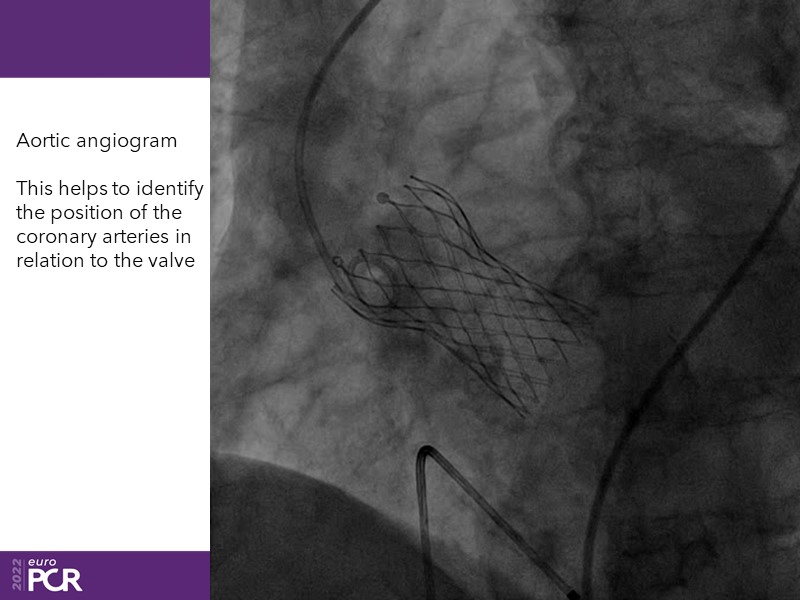

Consult this session to learn how to contribute to streamlined pre- and post-TAVI patient pathways, to discover updates on the optimised TAVI procedure and appreciate the variances in different valve designs and the long-term patient outcomes, as well as to discuss the right time of PCI in TAVI patients (steps on the procedure).